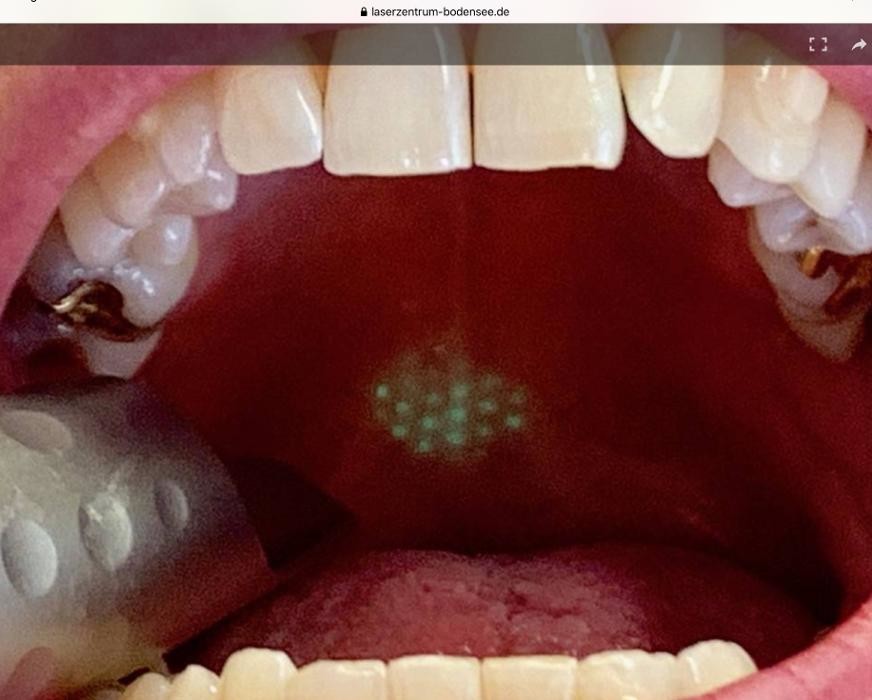

Mit weltweit höchsten Qualitätsstandards erhalten wir ihre Zähne ein Leben lang. Dafür setzen wir die besten weltweit verfügbaren Geräte in unserer zahnärztlichen Privatpraxis und dem angeschlossenen Laserzentrum-Bodensee ein. Mit unserem Spezialistenteam behandeln wir ergebnisorientiert und therapieren Karies und Parodontitis erfolgreich mittels schonendsten Lasertechniken.